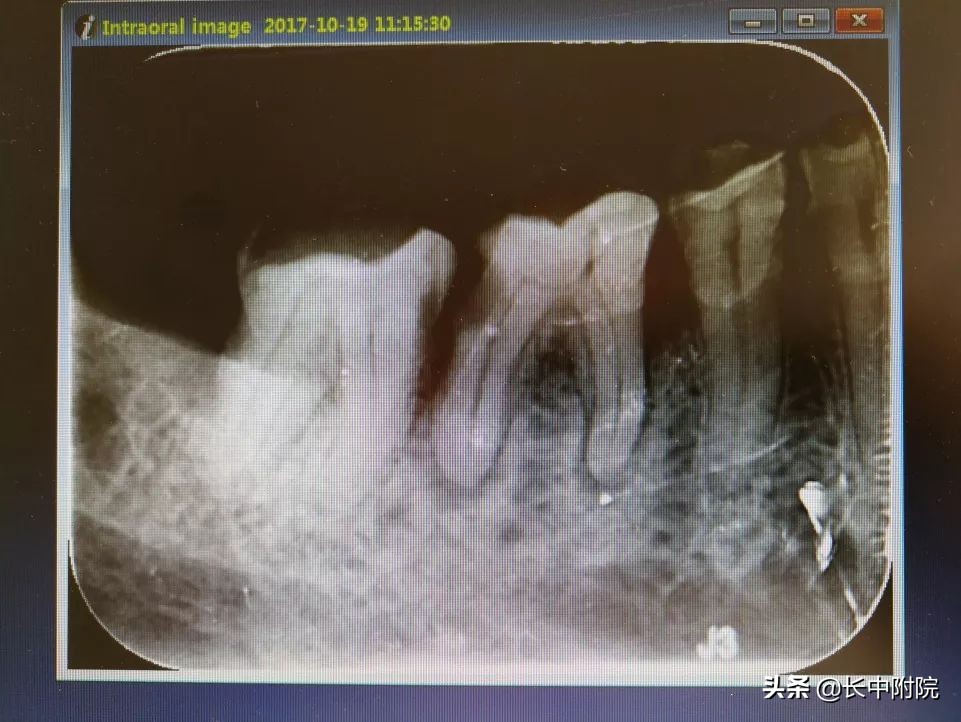

1.术前拍摄X线片

在根管治疗过程中,在根管治疗术前拍X线片,以帮助诊断,了解髓室的位置和根管数目及形态,测量根管工作长度及日后随访和评价疗效提供对比的依据。

应用平行投照X线方法、根管长度测量仪确定根管度,最好插针拍X片。

封闭整个根管系统、堵塞主根管和侧副根管出口、防止微生物和液体的渗漏。无论是侧方加压法还是垂直加压法,应做到根管充填致密,根管充填后X线片上无根管腔隙,也不能超出根尖孔。